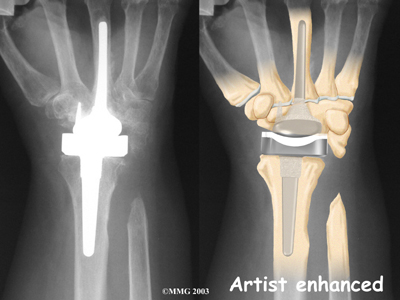

The wrist joint is replaced with an artificial joint (also called a prosthesis) much less often than other joints in the body, such as the knee or the hip. Still, when necessary, this operation can effectively relieve the pain caused by wrist arthritis. When severe arthritis has destroyed the wrist joint, artificial wrist replacement surgery (also called wrist arthroplasty) can help restore wrist strength and motion for many patients.

The main reason for replacing any arthritic joint with an artificial joint is to stop the bones from rubbing against each other. This rubbing causes pain. Replacing the

with an artificial joint gives the joint a new surface, which lets it move smoothly without causing pain.